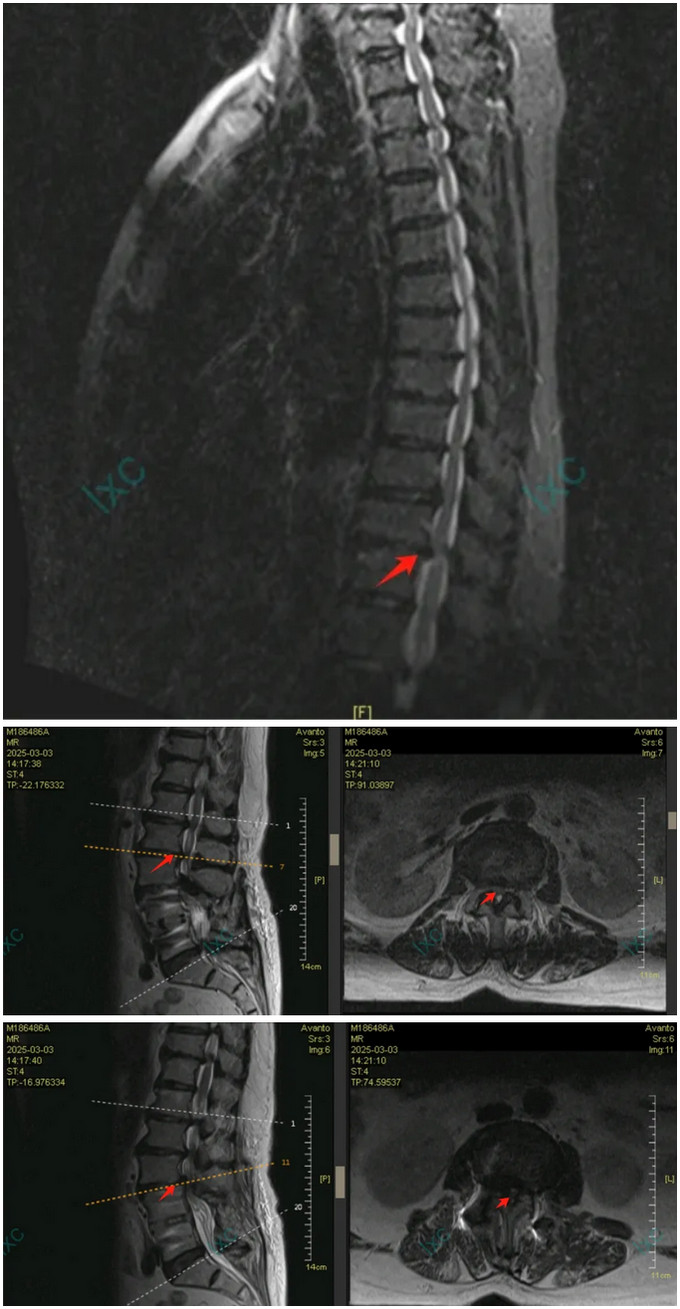

(胸椎MR显示T11-12节段脊髓压迫特写,及腰椎邻椎病变特写)

多学科会诊揭开了“双重瘫痪”之谜:胸椎T11-12节段椎间盘突出合并黄韧带钙化,已造成脊髓明显变性;而腰椎邻椎病变更像是“烟雾弹”。麻醉科王翔锋主任医师采用预存式自体血回输技术,为高龄患者筑起血液安全防线,为手术团队拆弹奠定坚实的后方阵地。

转机出现在今年初春。当邱女士右脚完全瘫痪时,通过港澳医疗界同行联系到黄播 王荣茂主任,林翔主任团队接诊后,敏锐发现患者除腰椎问题外,还存在进行性加重的中枢神经系统症状。“巴氏征阳性、下肢肌力仅1-2级,这提示存在脊髓层面损伤。”林翔主任医师回忆初诊时的关键判断。